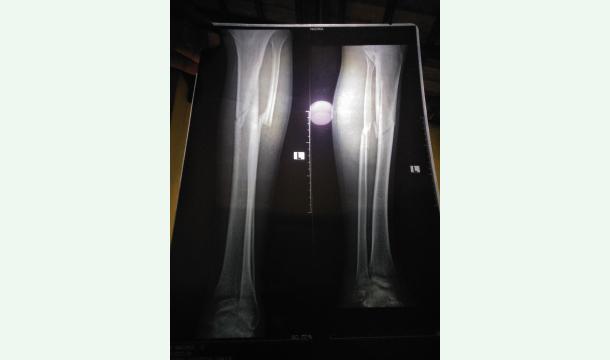

My leg was seriously broken in a car accident. I also lost my job. The surgery to fix my leg will take place in two weeks. It will cost 2.5 lakhs Sri Lankan rupees ($850). Your help is a great strength to me.